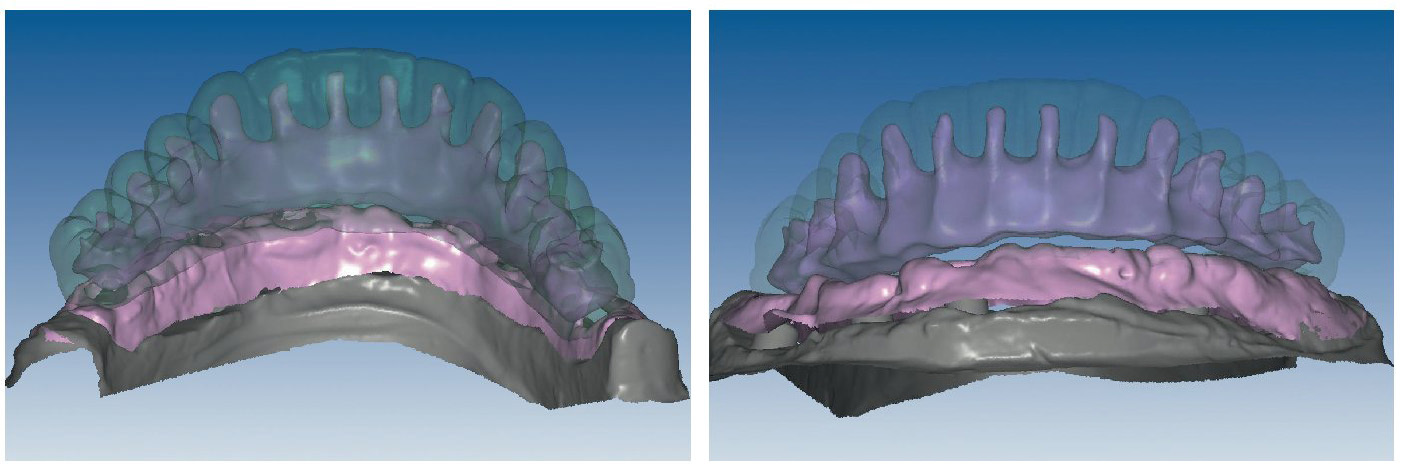

Mediante el uso de un escáner óptico de luz estructurada, los protocolos CAD registran los primeros datos relativos al modelo maestro con las correspondientes posiciones de implante (figs. 87 y 92). En el siguiente paso tiene lugar la digitalización de la planificación, previamente realizada en cera de escaneo matificada, de la restauración definitiva (figs. 88, 90 y 93). La subsiguiente conciliación de los datos mediante el uso del software de diseño dental permite al protésico planificar virtualmente el resto del procedimiento (figs. 89 y 91, 94 a 96) a partir del diseño de las estructuras (figs. 97 y 98).

Figs. 94 a 95. Planificación CAD de la estructura del maxilar inferior, en representación lingual y vestibular.

Figs. 96 a 98. El diseño definitivo de la estructura del maxilar inferior, desde distintas perspectivas.

Una vez aprobada la planificación, mediante el software CAD se transmiten los datos en formato STL (Standard Transformation Language o Stereolithography Language) a otro software CAM, el cual procesa nuevamente los datos suministrados para enviarlos en «idioma de máquina» a la fresadora (Zfx, ULTRASONIC 20, Denttec KG-SAS, Gargazon, Italia) encargada de confeccionar la estructura de titanio (figs. 98 y 99). La utilización de fresadoras industriales de cinco ejes para la confección de este tipo de prótesis garantiza un éxito seguro en cuanto a precisión de ajuste y pasivización, y evita casi todos los riesgos que pueden aparecer durante el colado protésico clásico.

Pese a ello, es importante someter las estructuras a un control visual y mecánico, a fin de corregir eventuales discrepancias menores (figs. 99 a 102). A continuación se procede al montaje utilizando dientes protésicos prefabricados de composite (SR Phonares NHC, Ivoclar Vivadent, Ellwangen, Alemania), los cuales reproducen el tipo funcional correspondiente en virtud de sus propiedades morfológicas y estructurales y se integran armoniosamente en cuanto a su longitud dental (figs. 103 a 105). Durante la comprobación de las restauraciones protésicas, se evalúan clínica y radiológicamente ante todo la pasividad y la precisión del ajuste de la estructura. Acto seguido se lleva a cabo una comprobación de la oclusión y de la dimensión vertical, del estado de las prótesis y del tejido blando en la cresta alveolar, así como la verificación del espacio libre lingual, incluida la fonación, y el apoyo de los labios y las mejillas (figs. 106 y 107). También se debe comprobar la facilidad de higiene de la restauración de acuerdo con las habilidades manuales del paciente. A continuación se debe verificar la posición tridimensional de los dientes anteriores con los labios cerrados y durante la sonrisa, así como el aspecto global de la rehabilitación protésica.